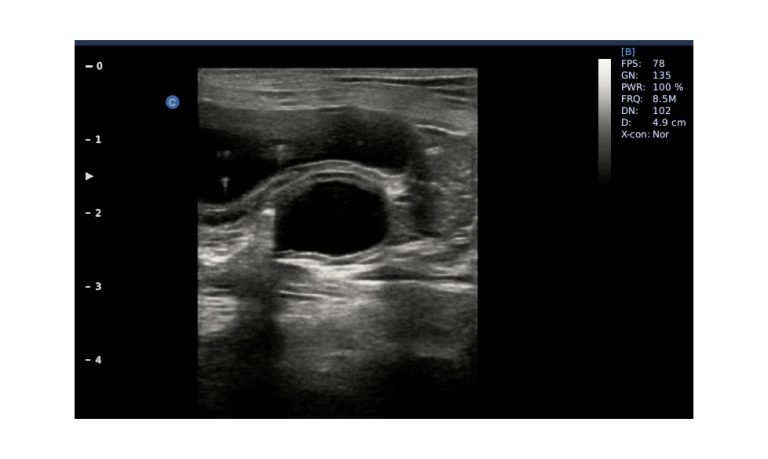

Ultrasound

Wide range of Ultrasound machines that suites a variety of applications from abdominal to rectal scans, we take in consideration how the world is moving towards mobility and mobile applications.